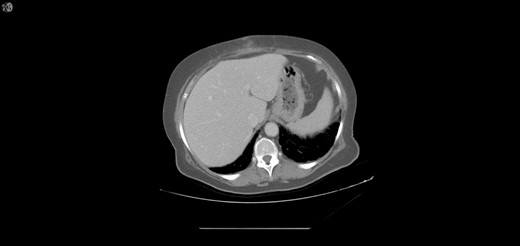

One year later, the patient was brought to the emergency department by her family for altered mental status. They reported 2 days of abnormal behavior and confusion culminating in an episode of bowel incontinence. The patient had difficulty following commands and was complaining of abdominal pain. Initial workup showed tachycardia, hypotension, leukocytosis and elevated creatinine which was treated per sepsis protocol. Her toxicology screen was positive for cocaine. Serum lactate was also elevated. CT brain without contrast showed no acute intracranial process. CT without contrast of the abdomen and pelvis, shown in Figs 3 and 4 , revealed dilated small bowel with gas in the bowel wall. Emergent damage control surgery was performed. There were no signs of gastrointestinal perforation but two segments of necrotic small bowel, 5 feet in total, were removed and the abdomen was sealed with Abthera. Two days later, her abdomen was re-explored and another 40 cm of non-viable small bowel was removed, leaving her with two small bowel anastomosis. Her abdomen was re-explored and closed after another 2 days. She was successfully weaned off the ventilator and continued to improve with supportive care. Final pathology examination revealed extensive necrosis with acute inflammation impacting the serosa at points in the small bowel.

Extensive pneumatosis of the small bowel during the second admission. Approximately 5 feet of ischemic bowel resected.